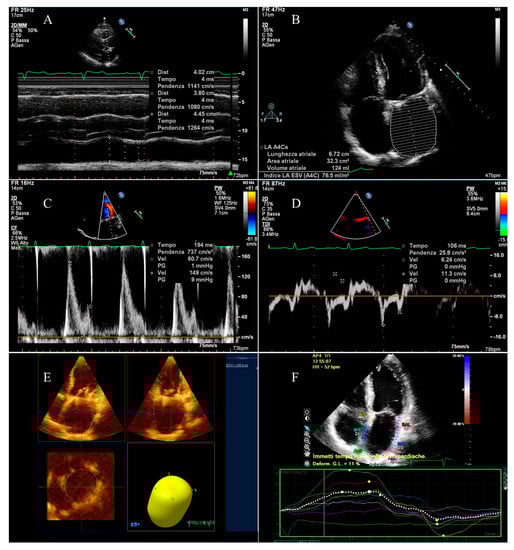

2.2. Echocardiographic Analysis

- Left atrial active emptying fraction, related to the LA booster pump function;

- Left atrial passive emptying fraction, describing the LA conduit function;

- Left atrial total emptying fraction, defining the LA reservoir function.